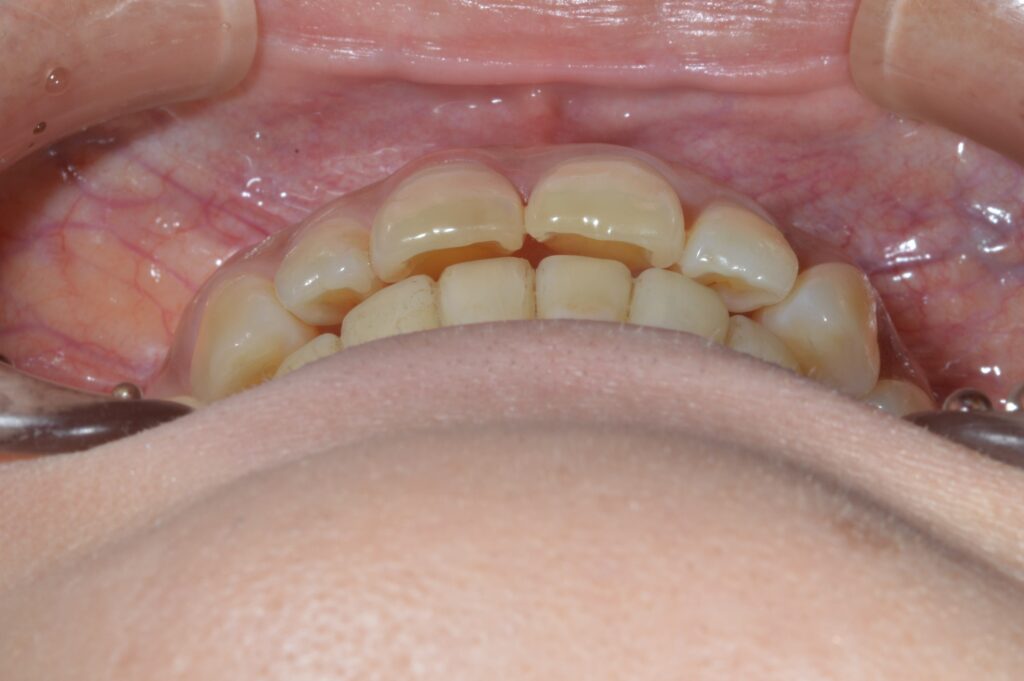

インビザライン(マウスピース矯正)にて上の前歯の重なりと下のデコボコを解消したケース

治療後

| 治療内容 | 上の前歯の重なりと、下のでこぼこの治療希望あり。インビザラインを用いて、矯正治療を行った。患者様はこちらの指示通り、確実にマウスピースを使用してくださった。微調整のため、追加アライナーの作成を2回行い、歯列が整ったので、保定に移行した。 |